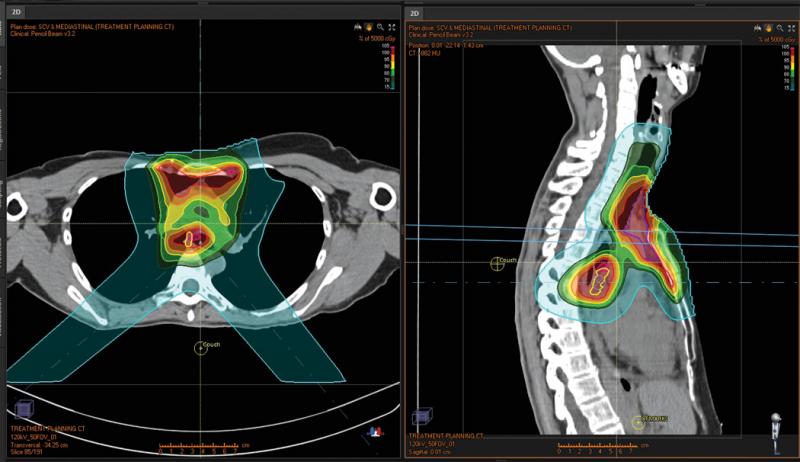

Figure 1: Original treatment plan

The patient in a second clinical case (Figures 3 and 4) had a clinical target volume (CTV) that was anterior on the sternum but also a CTV in the mediastinum behind the great vessels. A plan was designed to treat the anterior CTV with an AP beam and the posterior CTV with posterior obliques. However, the lung interface and the fact that the CTVs overlapped superior/inferior presented a challenge. Instead of treating single field uniform dose (SFUD) and irradiating more lung and heart tissue, robust optimization was utilized. This allowed the team to account for range uncertainty in a very heterogeneous area, and ensure that with setup error and range uncertainty there would be no unacceptable hot or cold spots. Uniform dose was achieved in a robust manner, even where the CTVs overlapped. Robust optimization further eliminated the need for beam specific PTVs and a complicated optimization process.